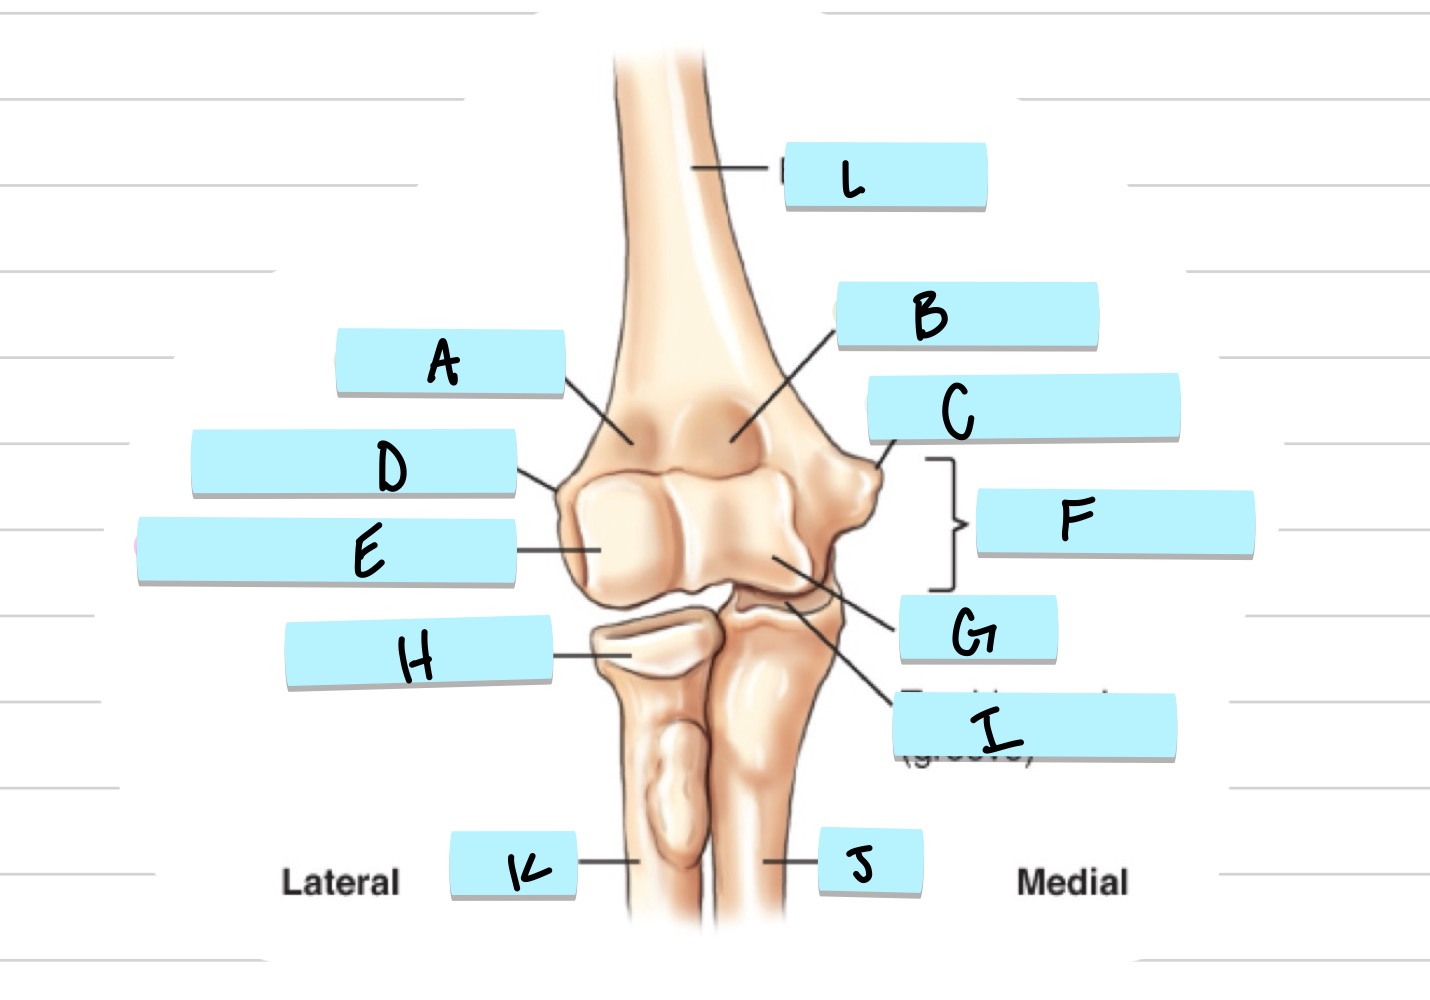

<p>what is A?</p>

what is A?

radial fossa

83

New cards

<p>what is B?</p>

what is B?

coronoid fossa

olecranon process

trochlear notch

37

<p>what is C?</p>

what is C?

coronoid process

38

<p>what is D?</p>

what is D?

radial notch